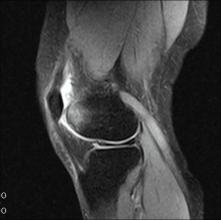

(二) 膝关节磁共振(magnetic resonance imaging )检查

膝关节 MRI 检查是对明确早期诊断、鉴别诊断、分期及确定治疗方法,很有价值的影像学“ 补充标准”,表现为膝关节的关节软骨厚度变薄、缺损, 骨髓水肿、囊性变、关节积液及腘窝囊肿。 有些病例还伴有半月板损伤及变性。

为便于制定规范的相对应阶梯治疗方案,本共识参考中华医学会《骨关节炎诊疗指南》(2018 年版) 提出 KOA 分期标准。 标准中的临床症状和体征包括膝关节疼痛、活动、肿胀和畸形 4 个方面 ,其中患者的主观疼痛为主要标准 。 本共识使用视觉模拟评分法( visual analogue scale,VAS) 评价疼痛严重程度( 附件 1),同时将客观影像学检查作为确诊标准,其中 X 线片表现为基本标准,磁共振为补充标准。 以目前临床上应用最广泛的Kellgren-Lawrence ( K-L) 分级作为 X 线片表现的分级标准 ( 附件 2)。 膝关节核磁共振表现以 Recht分级作为标准 ( 附件 3)。

当患者主观疼痛等级严重、X 线片表现 K-L 分级较低,二者不符合时,核磁共振检查作为补充标准,以其分级为准。

KOA( 膝骨关节炎) MRI 检查的 Recht 分级标准

由于 OA 早期表现为软骨退变或剥脱、软骨下骨水肿等,单纯X线往往不能准确反映疾病的严重程度,导致单凭X 光片往往难以区分极早期与早期 OA 患者,因此在临床遇到 X 线退变表现与疼痛强度明显不符的情况时,推荐患者接受MRI 检查,并根据 MRI 检查结果进行再评估。 对早期评估难以分级的患者进行 MRI 检查的影像学结果,推荐使用 Recht 分级进行再评估。

0 级 正常软骨,软骨弥漫性均匀变薄但表面光滑。

Ⅰ级 软骨分层结构消失,软骨内出现局灶性低信号区,软骨表面光滑。

Ⅱ级 软骨表面轮廓轻至中度不规则,软骨缺损深度未及全层厚度 50%。

Ⅲ级 软骨表面轮廓中至重度不规则,软骨缺损深度达全层厚度 50%以上,但未完全脱落。

Ⅳ级 软骨全层缺损、剥脱,软骨下骨质暴露,有或无软骨下骨骨质信号改变。